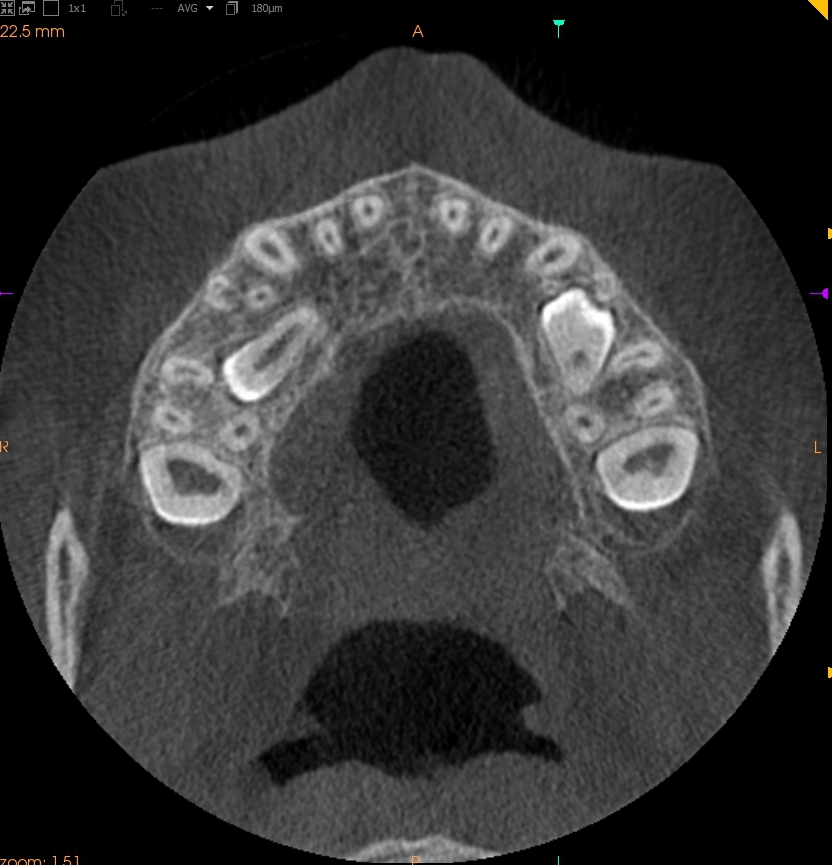

Resorpcja zęba to proces powstania ubytku twardych struktur zęba wywołanego przez osteoklasty bez kontaktu ze środowiskiem jamy ustnej, między innymi na skutek ucisku wywieranego przez ząb zatrzymany. Dla lekarza ortodonty jest istotne ustalenie, czy zęby zatrzymane lub twory nadliczbowe powodują resorpcję zębów stojących w łuku w celu wczesnej eliminacji przyczyny resorpcji. Celem pracy jest przedstawienie opisu przypadku zastosowania tomografii stożkowej w diagnostyce nieprawidłowo położonych zawiązków zębów przedtrzonowych drugich górnych. Stwierdzono, że tomografia stożkowa jest skuteczną metodą oceny wczesnej resorpcji zewnętrznej korzeni zębów.

Tooth resorption is the process of appearing of a defect of hard tissues of teeth caused by osteoclasts not having contact with oral cavity environment, eg. due to mechanical pressure exerted by an impacted tooth. It is essential for an orthodontist whether impacted teeth or supplementary teeth cause resorption of erupted teeth in order to early eliminate the causative factor of the resorption. The aim of the paper is to describe a case report of cone-beam computed tomography (CBCT) in diagnostics of incorrectly located germs of upper second premolars. It was found that CBCT was an efficient method of imaging of early external root resorption.